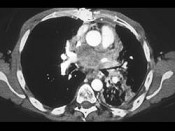

单项选择题男,45岁, 咳嗽,咯血2月余, 有20余年吸烟史,请结合影像学检查, 选出最可能的诊断 ( )

A、肺结核

B、小细胞肺癌

C、肺脓肿

D、肺囊肿

E、肺错构瘤